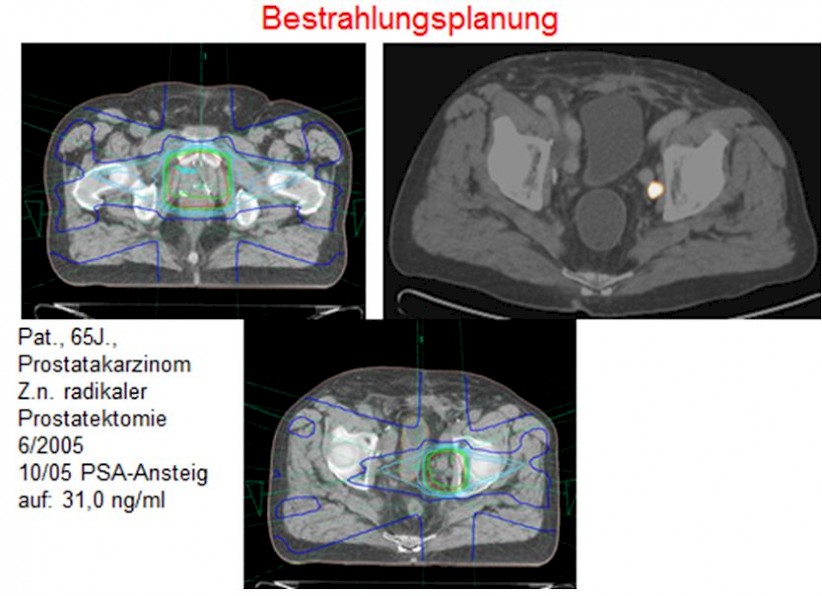

- -FDG eignet sich nicht zur Darstellung von Prostatakarzinomen. Deshalb wird bei der Prostatadiagnostik -Cholin verwendet. Das PET-CT-Verfahren ist beim Re-Staging sinnvoll, da sich bei steigendem PSA-Wert oft fehlende oder unsichere Befunde in der CT ergeben.

- F-18-Cholin bei der Prostatakarzinomdiagnostik